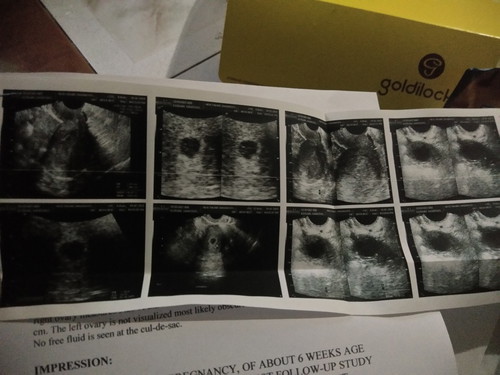

6WEEKS

Mga sis ask ko lang ano yung gestational sac pa lang siya? Balik daw ako 1-2 weeks

Ibig sabihin po bahay bata palang pero wala pang laman. Yung iba po talaga di pa nakikita kase maaga pa, mga 8-10 weeks po nakikita kadalasan